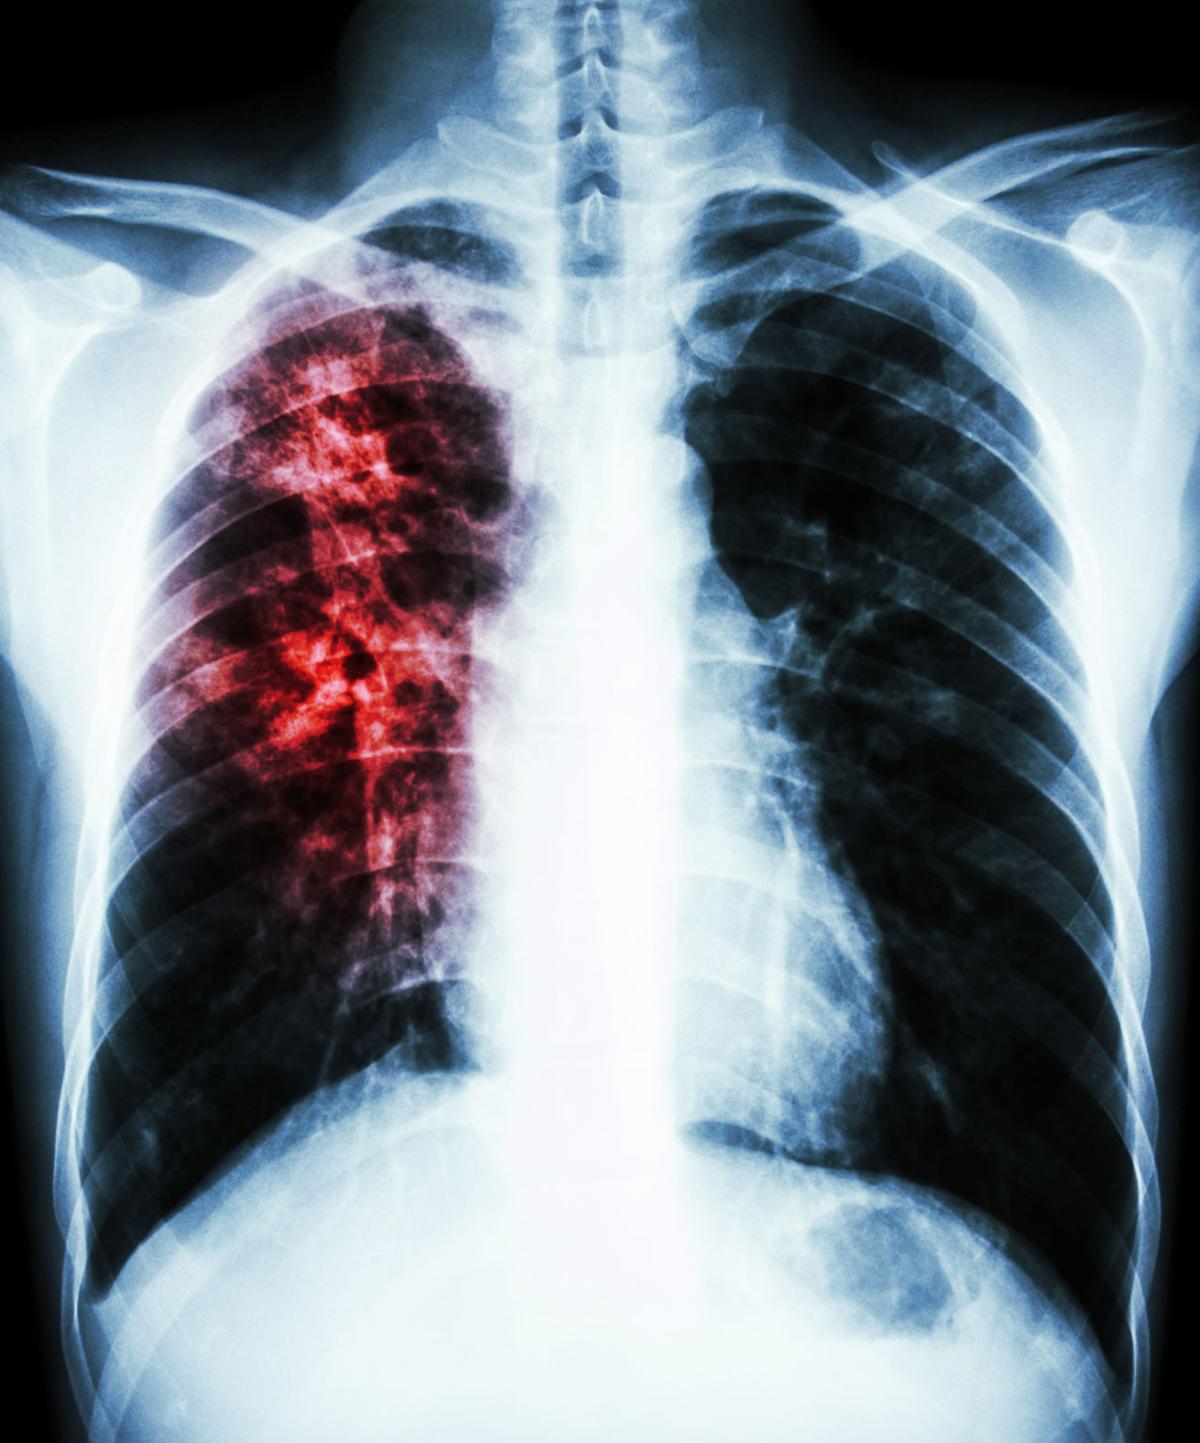

Снимок легких при туберкулезе является важным методом диагностики этого заболевания. На рентгеновских снимках можно увидеть изменения в легких, которые свойственны туберкулезу.

Очаговый туберкулез рентген

Рентген грудной клетки туберкулез

Фотографии снимков легких при туберкулезе

В данной статье представлены многочисленные фотографии снимков легких при туберкулезе, чтобы помочь вам понять, как выглядят изменения легких на рентгеновских снимках при этом заболевании.